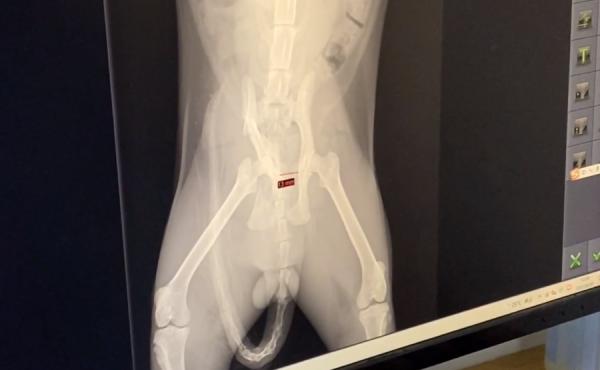

隨後,貓咪的拍片結果也出來了,而在這個拍片結果裡,寵物醫生髮現,貓咪的一側骨盆脫臼,一側骨盆骨折,顯然這是車禍引起的,正當小姐姐和寵物醫生商量貓咪的手術方案時,原本將貓咪從高架橋上救下來心裡一直都沒什麼波瀾的小姐姐,在看到寵物醫生研究貓咪手術方案時,貓咪看向她的眼神時,小姐姐瞬間破防了……